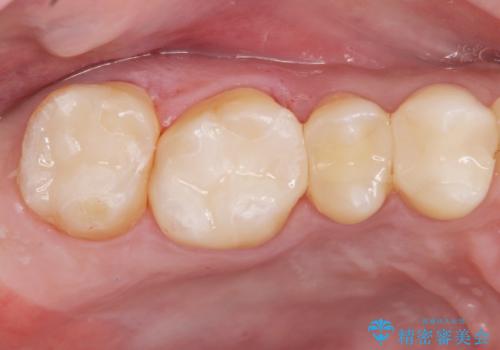

[ 歯並びと虫歯治療 ] 矯正治療とセラミック治療の包括治療

![[ 歯並びと虫歯治療 ] 矯正治療とセラミック治療の包括治療の症例 治療後](https://seimitsushinbi.jp/wp/wp-content/uploads/2023/12/d2649953cbde2ed7237dd47483ac69db-1-500x350.jpg?v=1703058723)